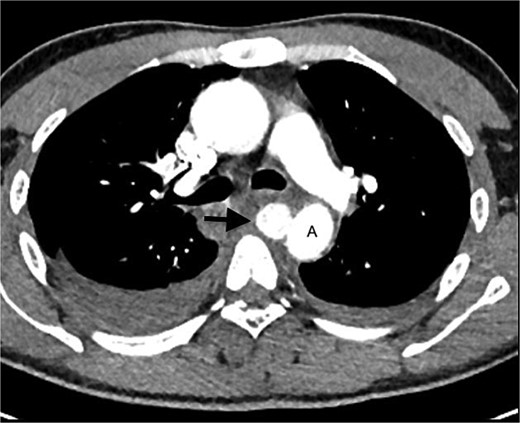

The MRI also revealed a well-circumscribed lesion in the posterior mediastinum at the T4–5 level, inseparable from the medial aspect of the mid-thoracic aorta, at the level of the penetrating wound (Fig. 2b). These findings were concerning for a traumatic aortic injury, and the patient was therefore referred for an urgent computed tomography (CT) angiogram of the chest. The CT angiogram confirmed a pseudoaneurysm of the descending aorta, 3 mm in diameter, associated with a mediastinal hematoma and bilateral haemothoraces (Fig. 3). In retrospect, the aortic injury was an incidental finding. The vascular surgery team was consulted, and the patient was booked for an endovascular thoracic aorta repair on the following elective surgical list. The patient was admitted to our high care unit for monitoring while awaiting theatre. A labetalol infusion was initiated to control his blood pressure, and appropriate analgesia was administered. He remained haemodynamically normal during admission, and his haemoglobin level did not fall.

CT angiogram of the chest confirms a pseudoaneurysm (arrow) of the thoracic aorta (A), with surrounding mediastinal haematoma and bilateral haemothoraces.